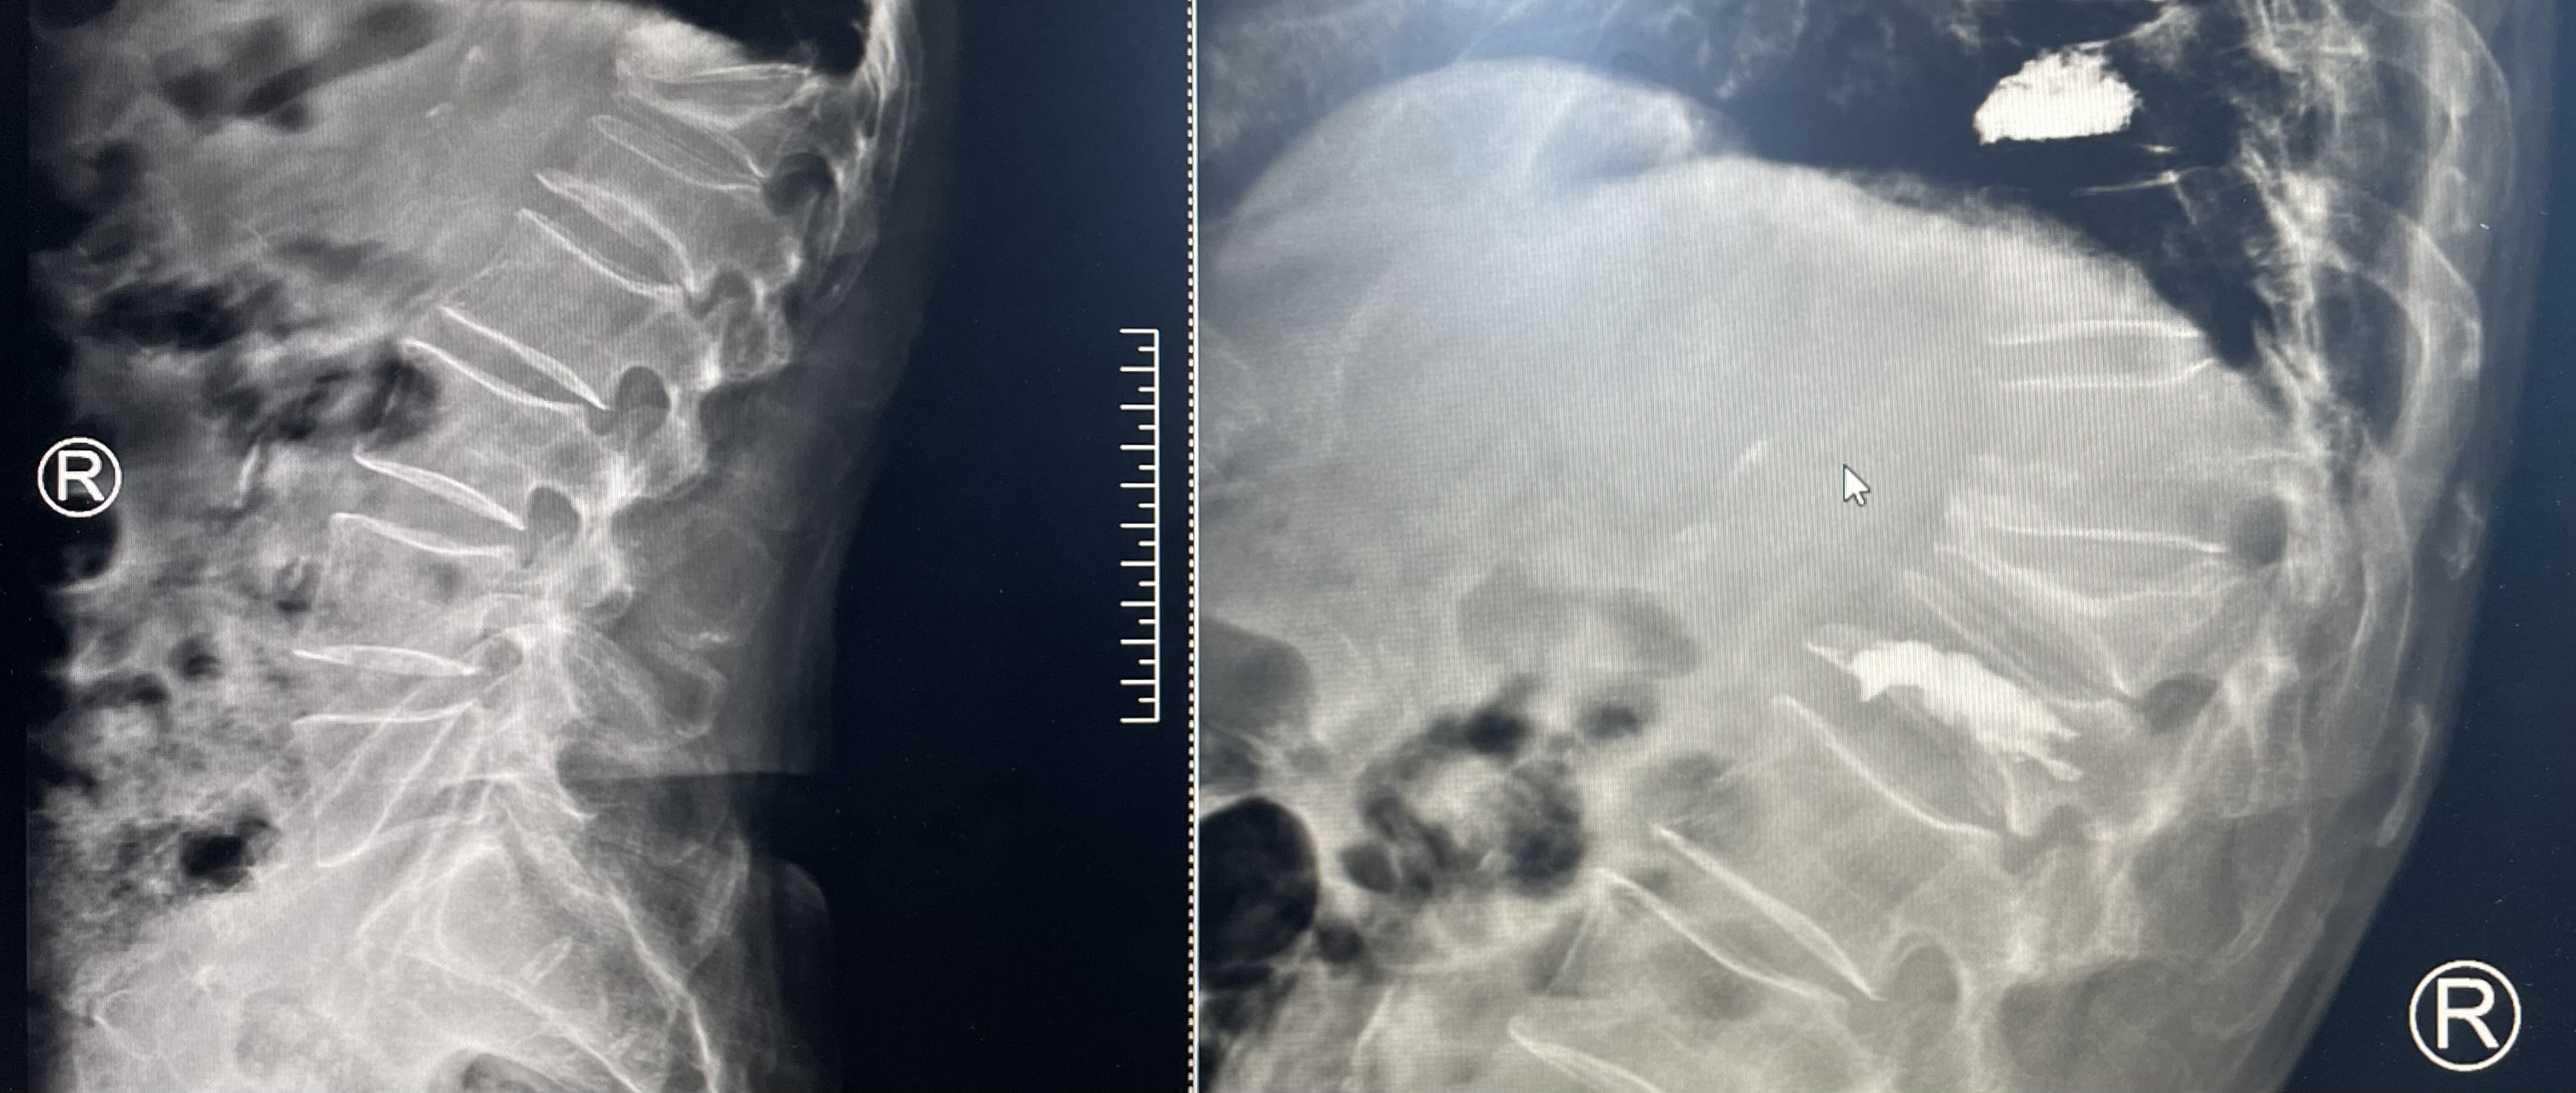

首先,尚主任仔细看了王大爷的检查报告,发现腰椎有两处骨折,询问病史后,考虑为老年人骨质疏松引起的椎体骨折,需要进行椎体成形术。

然后,尚主任为患者及家属详细地讲解了手术过程。只需要在腰部骨折处做一个约2mm的切口,通过穿刺针将“骨水泥”注入椎体内,凝固几分钟,加强椎体强度,缓解疼痛。